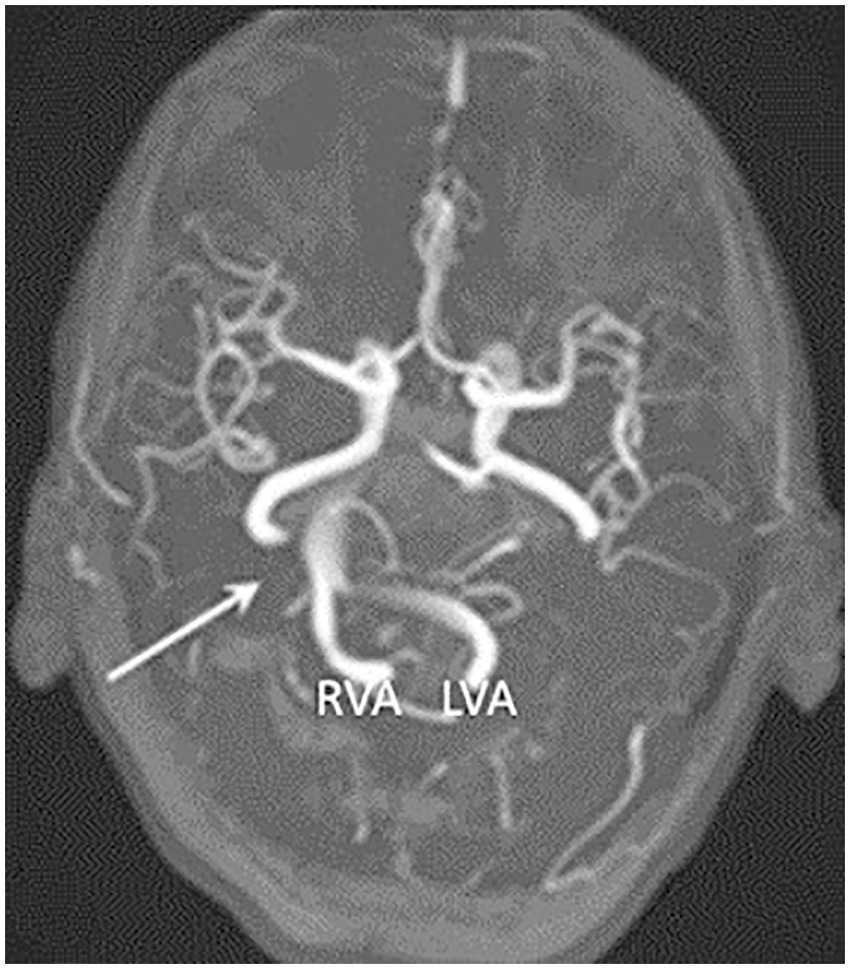

Dolichoectasia most frequently affects the brain posterior circulation, and in these cases, is known as vertebrobasilar dolichoectasia (VBD) (6). Considering the close anatomical relationship between the arteries of the posterior circulation and the brainstem with cranial nerves originating there, changes in the dimensions and location of the vertebrobasilar system can cause compressive symptoms on these structures. Cases of trigeminal neuralgia and hemifacial spasm caused by arterial compression, as well as hydrocephalus caused by obstruction of cerebrospinal fluid flow, have been documented (5, 10). VBD has also been associated with an increased risk of different types of hemorrhagic and ischemic cerebrovascular diseases of the posterior circulation, which are considered the most frequent complications associated with this condition (11). Figure 1 shows a case of VBD reported for Wang et al. (10).

Figure 1. Case report of vertebrobasilar dolichoectasia published by Wang et al. (10), showing, by time-of-flight magnetic resonance angiography (TOF-MRA), a dilated and laterally displaced basilar artery (arrow) reaching the right cerebellopontine angle cistern. RVA: Right vertebral artery. LVA: Left vertebral artery. Image licensed under Creative Commons Attribution 4.0 International (CC BY 4.0), and modified for presentation in this article.